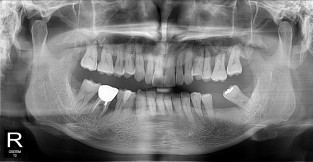

하악

치료기간 : 2021-11-30 ~ 2022-07-13

1. 상기 x-ray 이미지 모두 동일한 해당 의료기관에서 진료한 환자입니다.

2. 상기 x-ray 이미지 모두 동일 인물의 것입니다.

3. 치료 전 이미지는 2021-11-30에 촬영했으며, 치료 후 이미지는 2022-07-13에 촬영하였습니다.

4. 상기 x-ray 이미지 모두 동일 조건에서 환자분의 동의를 받아촬영되었습니다.

* 임플란트 시술은 환자분의 상태(고혈압, 당뇨 등)에 따라 부작용이 있을 수 있으니, 반드시 전문의와 상담이 필요합니다.

* 임플란트 수술 부작용

: 수술 후 출혈, 교합, 통증, 붓기, 염증 등의 문제점이 발생할 수 있습니다.)